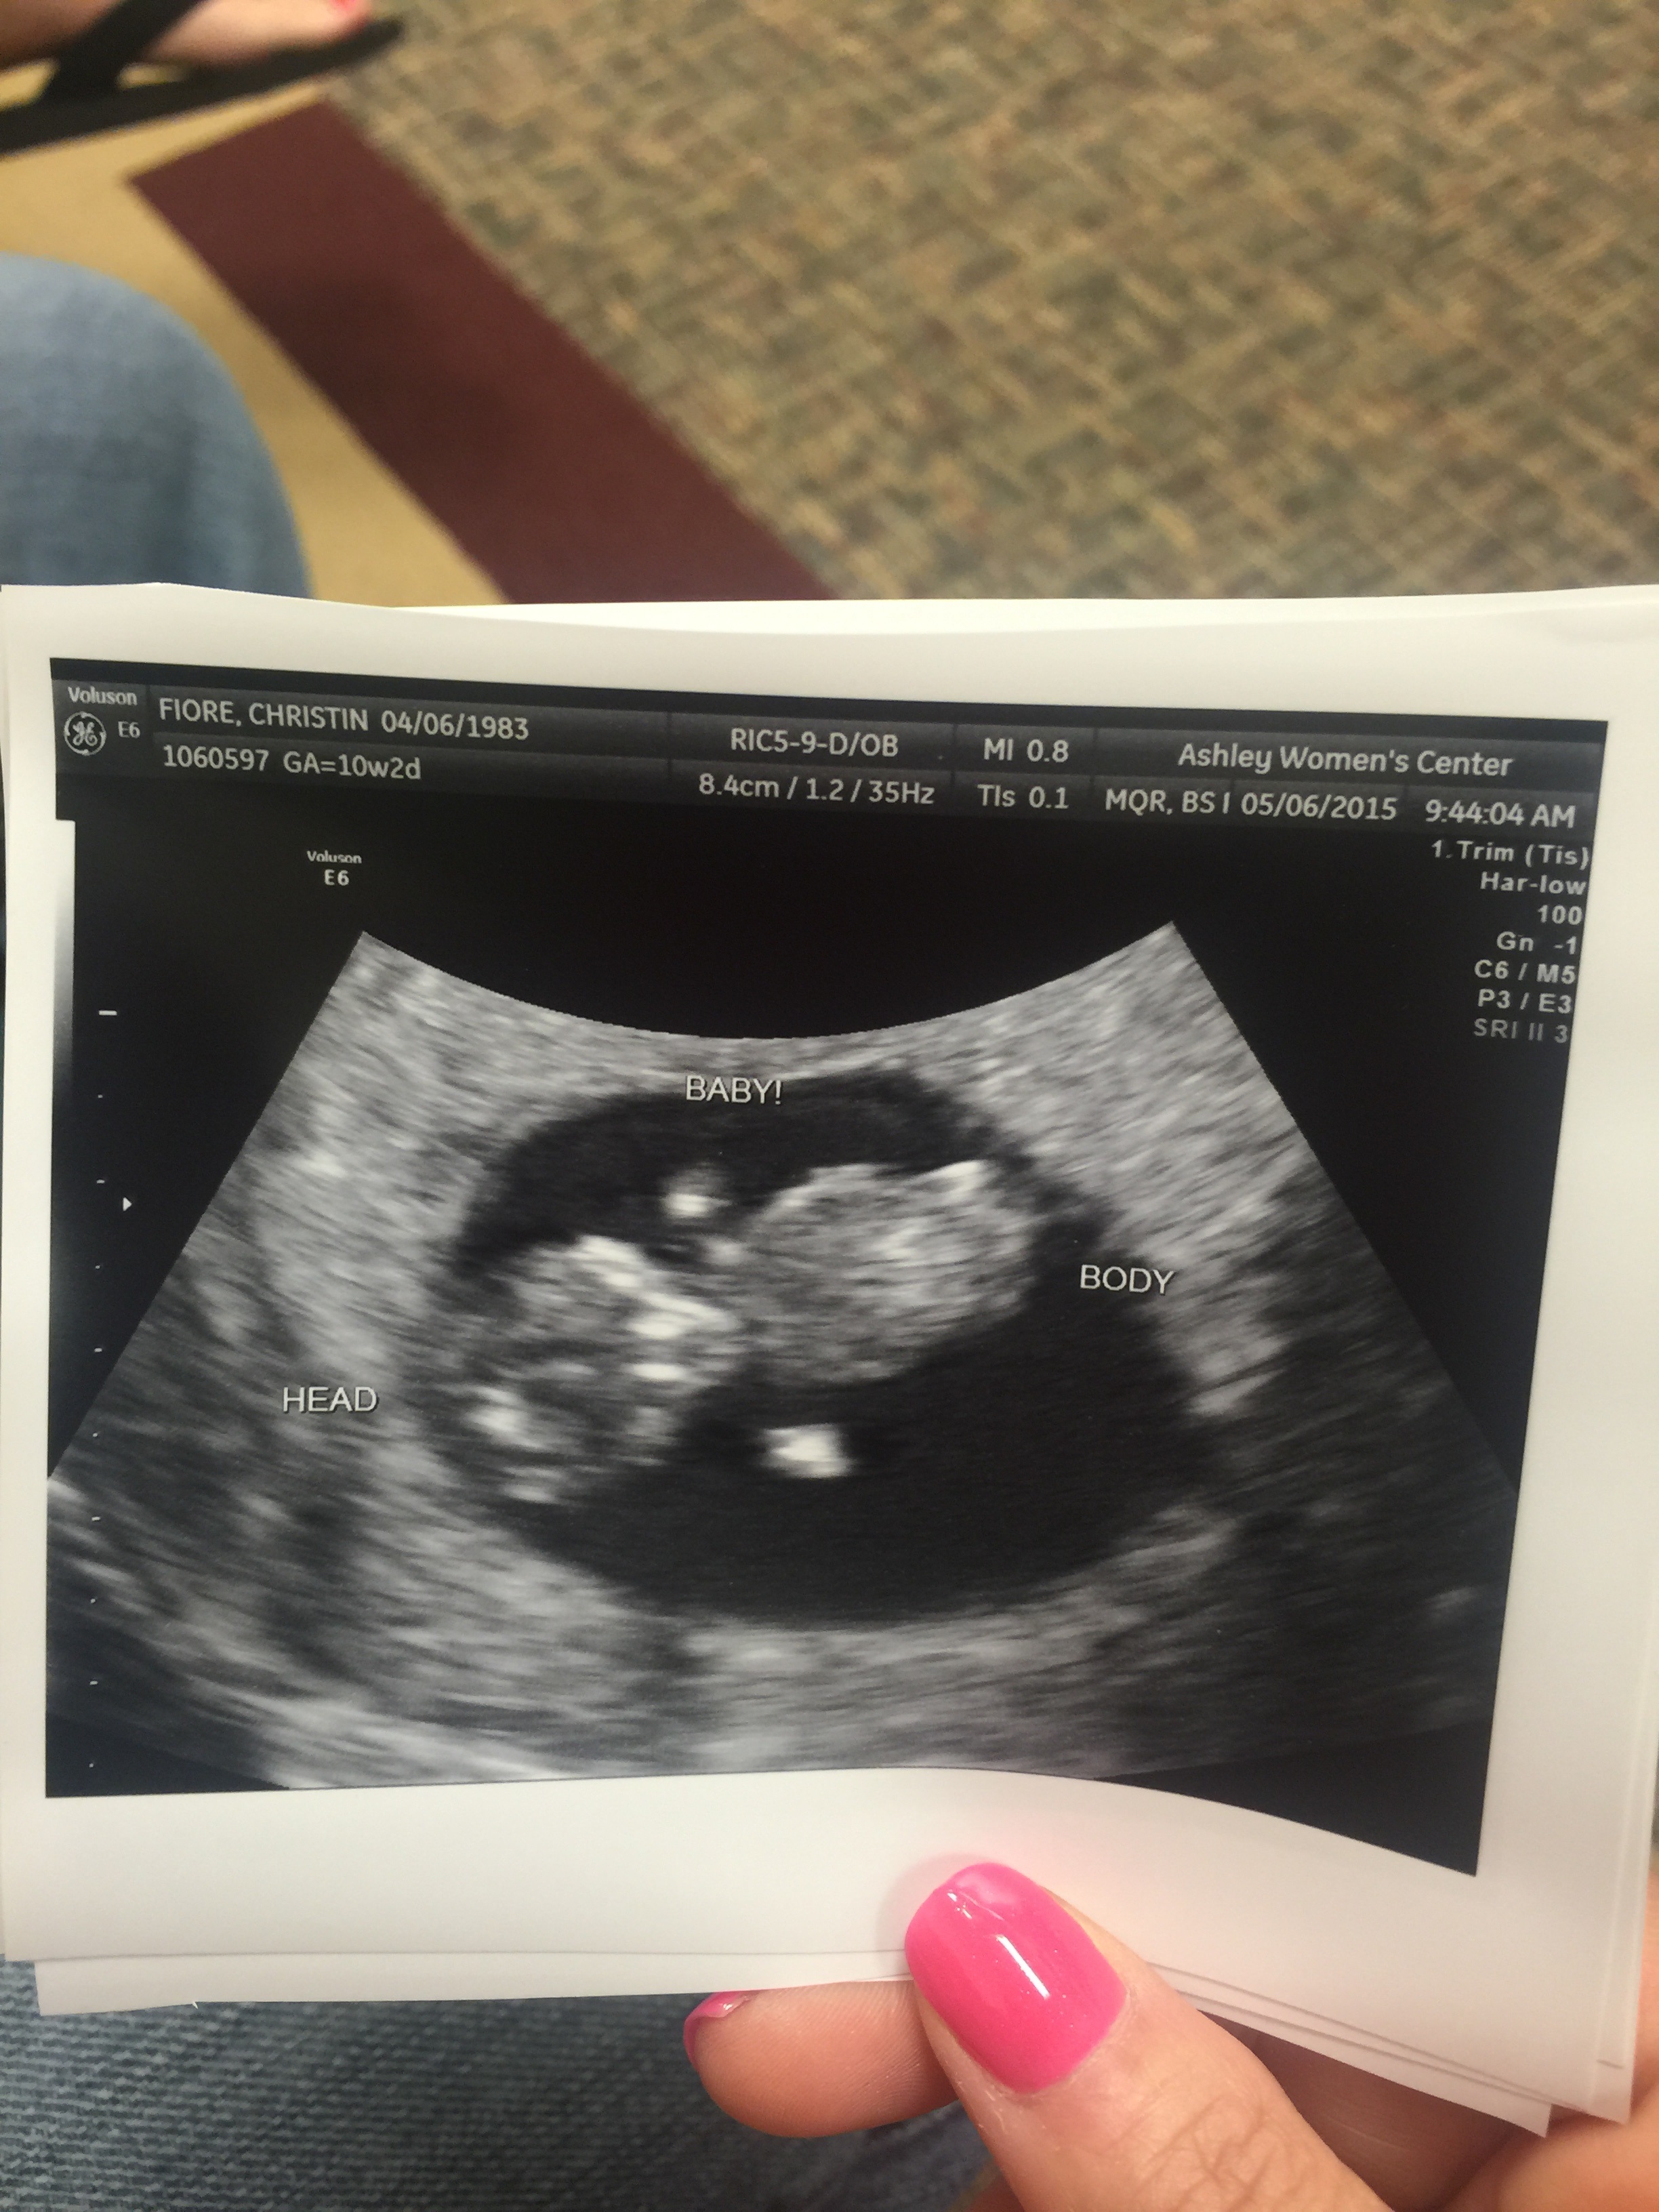

I was too busy crying and excited during the ultrasound appointment today I forgot to ask which size the placenta was on. I have no idea what I'm looking for and have tried looking at tons of other pics and am still clueless. Can anyone Ramzi me? Pretty please :)

Attachment 25102